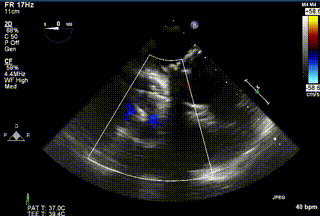

2021年12月24日,復(fù)旦大學(xué)附屬中山醫(yī)院葛均波院士團(tuán)隊(duì)成功應(yīng)用LuX-Valve Plus為一例極重度三尖瓣反流(TR)合并房顫、房缺的患者完成了經(jīng)血管三尖瓣置換術(shù),這是在前基礎(chǔ)上,本周完成的第三例經(jīng)血管三尖瓣置換手術(shù),葛均波院士、周達(dá)新教授等與心外科魏來(lái)教授、賴顥教授,心超室的潘翠珍教授、李偉教授及麻醉科的郭克芳教授共同完成了本周手術(shù),均獲得圓滿成功!患者術(shù)后超聲顯示無(wú)TR,臨床癥狀明顯改善。本周手術(shù)的成功也為L(zhǎng)uX-Valve Plus救治性臨床研究添上了濃墨重彩的一筆。

三例患者入院后,葛均波院士團(tuán)隊(duì)周達(dá)新教授、潘文志教授、張?jiān)床┦?、陳莎莎博士及心超室的潘翠珍教授、李偉教?/strong>對(duì)患者的情況進(jìn)行詳細(xì)評(píng)估和討論,最終決定為三例患者選擇LuX-Valve Plus40mm、50mm和50mm型號(hào)的瓣膜進(jìn)行手術(shù)治療。手術(shù)后即刻拔除氣管插管,術(shù)后患者三尖瓣反流癥狀得到顯著改善,復(fù)查心超結(jié)果顯示人工三尖瓣瓣膜支架固定穩(wěn)定,瓣葉關(guān)閉形態(tài)未見(jiàn)異常,未見(jiàn)明顯反流。